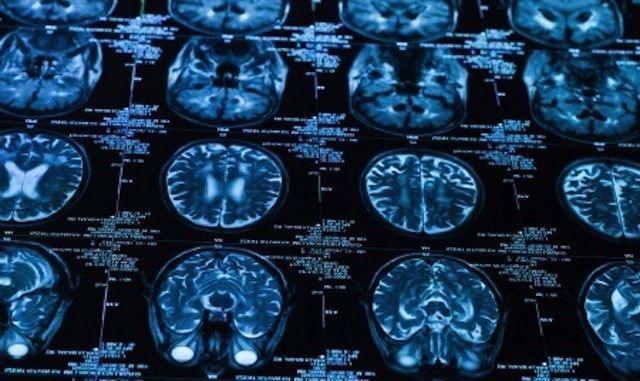

Player safety has become a hot topic around the NFL in recent years, particularly when it comes to concussions and other head injuries.

Last spring, two former NFL players — Ray Easterling, a safety for the Atlanta Falcons in the 1970s, and Junior Seau, a linebacker who played 20 seasons in the NFL for three teams (the San Diego Chargers, the Miami Dolphins, and the New England Patriots) and who played in 12 Pro Bowls and two Super Bowls — committed suicide within just two weeks of each other. Long term effects of repeated concussions are believed to have been related to both incidents.

The suicides followed that of Dave Duerson, a former defensive back for the Chicago Bears, who committed suicide two years ago. Duerson requested that his brain be donated to to researchers exploring the links between repeated concussions and other brain injuries. According to reports, Duerson was aware of a condition known as chronic traumatic encephalopathy (often referred to as C.T.E.) and an anonymous source reported that before his death, he had expressed concern that he might have C.T.E.

A formal diagnosis of C.T.E. can only be made by examining the brain after death, though research as recent as this month indicates that it may be possible to identify the disease using a PET scan).

Both Duerson and Seau were found to have C.T.E. during examinations of their brain tissue last year.

C.T.E. is a degenerative and incurable condition associated with repeated head trauma that can include memory loss, dementia, impaired cognitive function, and depression as well as other emotional and psychological symptoms – including an increased risk of suicide.

Its link to repeated blows to the head was initially dismissed or discredited by NFL officials and physicians, though it has gained acceptance in recent years, perhaps because of growing evidence of the condition among combat veterans.

A recent scientific study, published in the journal Brain in December, bolstered the link between repeated concussions and mild traumatic brain injury. The study examined the brains of 85 people, 68 of them (80%) men, including 33 former NFL players and 17 non-NFL football players. The study was the first to categorize the stages and progression of the disease, but it wasn’t able to conclusively demonstrate a link between C.T.E. and on-field injuries. Nor was it able to predict the risk NFL players have for developing the disorder nor explain why some players develop it while other don’t.